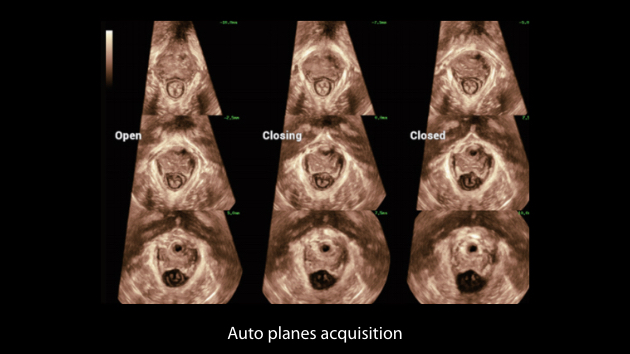

The Nuewa I9 Elite Edition, dedicatedly designed for women and neonatal healthcare, providing an innovative experience from inside out. These innovations are developed based on in-depth insights into complex clinical scenarios, providing accurate and timely answers as well as outstanding efficiency and remarkable user experience